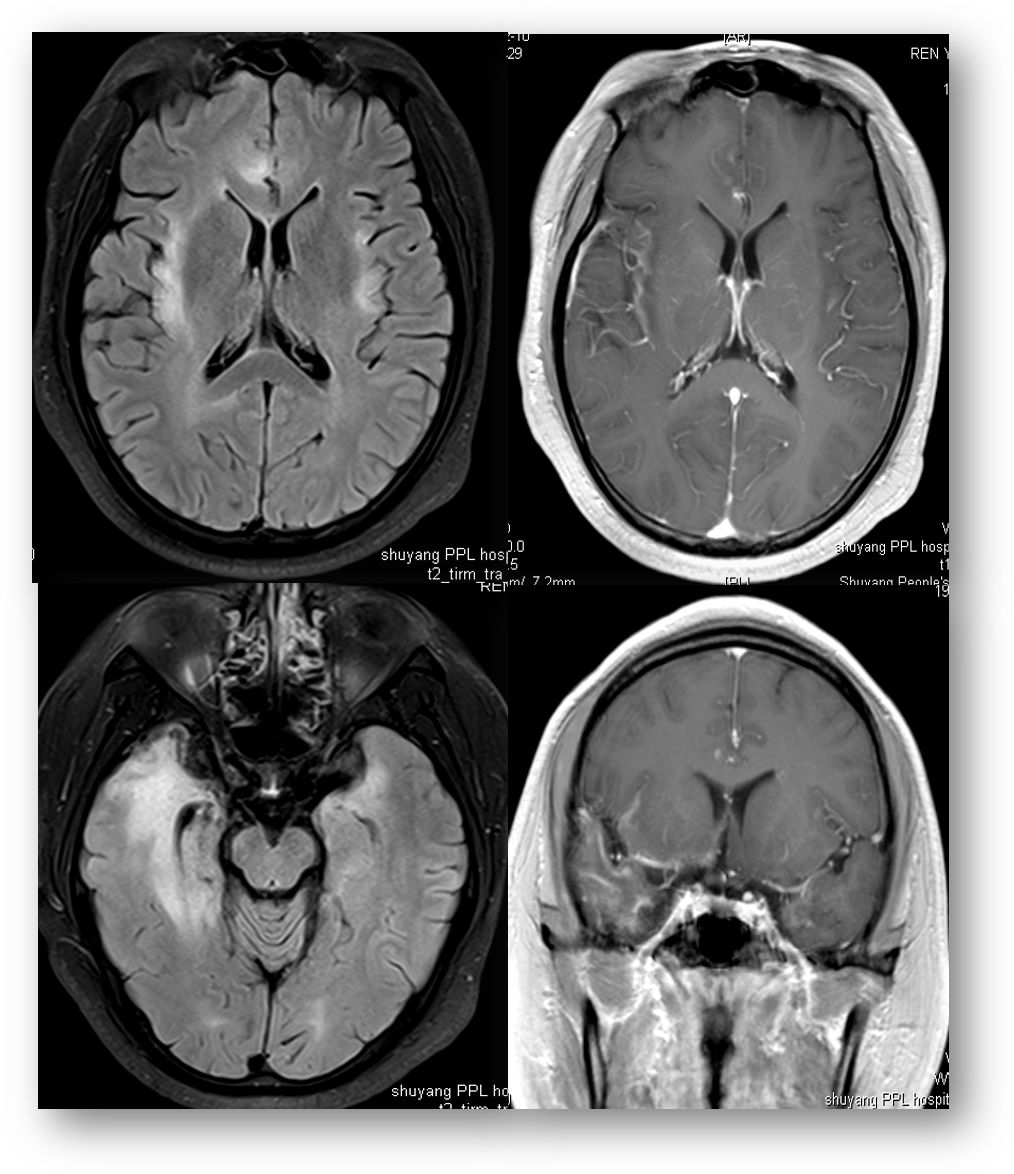

30岁,男。发作性意识不清伴肢体抽搐7个月、反应迟钝5个月,视物不清、听力下降3个月。

头颅MRI提示:双侧颞、枕、顶、额叶以及海马大片异常信号,FLAIR高信号,增强可见明显沟回样、片状强化,主要以皮层和皮层下为主,深部白质亦有波及。

诊断: Whipple病。

头颅MRI:脑萎缩、颅内多发或孤立肿块、脑膜浸润、灰白质交界处弥漫病变和脑积水等。占位效应和水肿可有可无。T1WI大小不等、形状不规则高信号,部分脑回变窄、脑沟增宽。T2WI可见多发大小不等片状高信号影,其内信号不均匀。FLAIR多呈高信号, DWI略高及等信号。SWI脑内可见多发类圆形大小不等圆形低信号影。增强:均匀、环状、斑片状强化。MRS:Cho增高, Cr、 NAA降低, Cho/ Cr>>1。